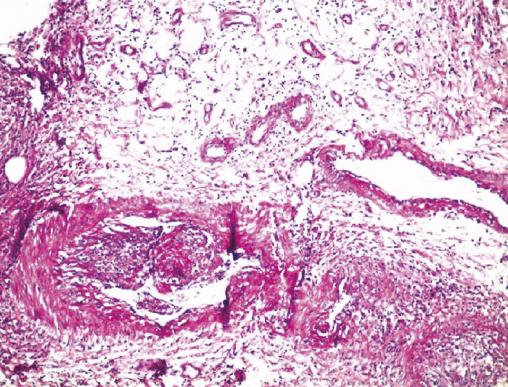

Cette femme de 50 ans sans antécédents notables était hospitalisée pour des ulcères chroniques des membres inférieurs. Six mois auparavant, des nodules fermes indolores étaient apparus au niveau des membres inférieurs, évoluant vers la fistulisation et la confluence, et donnant lieu à de nombreux ulcères. L’examen clinique notait de multiples ulcères des membres inférieurs nécrosants, surinfectés et creusants, à bordure, surélevés, mimant un pyoderma gangrenosum (fig. 1), sans arthralgies ni myalgies. Le bilan biologique montrait un syndrome inflammatoire biologique, le bilan auto-immun était négatif, de même que les sérologies des hépatites B et C et du VIH, l’échographie doppler artérielle et veineuse, et le bilan de systématisation. L’étude histologique (fig. 2) confirmait le diagnostic de périartérite noueuse. La patiente était traitée par des bolus de méthylprednisone avec un relais par la prednisone 1 mg/kg/j per os, associée à une seule cure de plasma riche en plaquettes. L’évolution était marquée par un début d’amélioration clinique, mais la patiente était ensuite perdue de vue.

La périartérite noueuse associe classiquement une altération de l’état général fébrile avec arthromyalgie, mononévrite et des atteintes cutanées, rénales ou digestives. Il s’agit d’une affection rare survenant à tout âge, parfois associée à des infections, comme l’hépatite B.1 Elle atteint pratiquement tous les organes. L’atteinte cutanée est notée dans 10-15 % des cas avec principalement un purpura pétéchial infiltré.2 Le mode de révélation par des ulcères chroniques nécrosants et creusants des membres inférieurs n’est pas fréquent. La biopsie cutanée confirme le plus souvent le diagnostic montrant une vasculite leucocytoclasique et nécrosante des vaisseaux de petit et moyen calibre.3 Le traitement est la corticothérapie, parfois associée à des immunosuppresseurs. L’établissement d’une stratégie thérapeutique ne se conçoit qu’en milieu spécialisé et de façon adaptée à la gravité de la maladie.